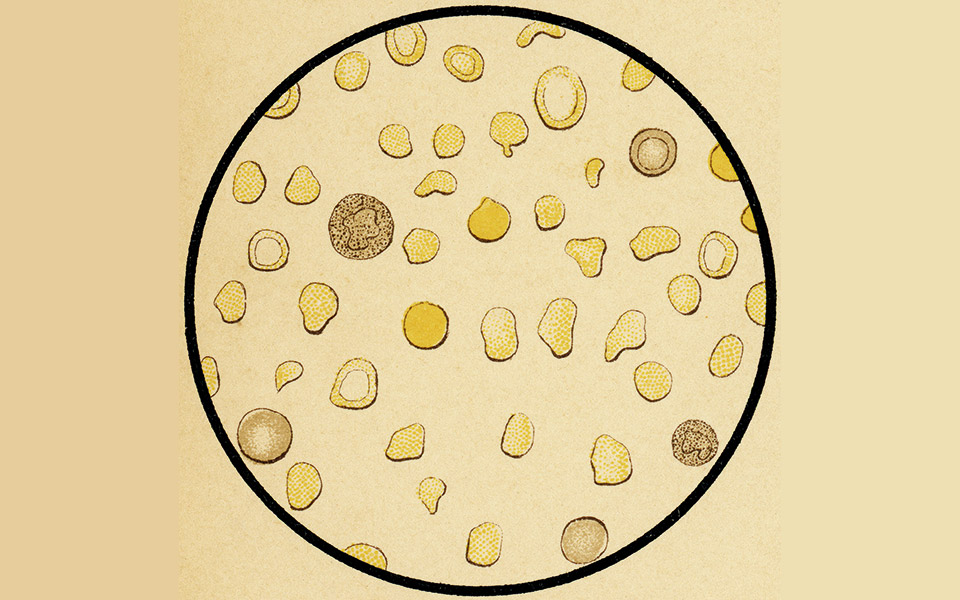

Η β-θαλασσαιμία (ή μεσογειακή αναιμία) είναι μια αιματολογική νόσος με αυξημένη συχνότητα στη Μεσόγειο. Χαρακτηρίζεται από τη μειωμένη ή παντελή έλλειψη της αιμοσφαιρίνης Α, μιας μεταλλοπρωτεΐνης που μεταφέρει το οξυγόνο στους ιστούς, λόγω αδυναμίας σύνθεσης των β-αλυσίδων της. Ως εκ τούτου παράγονται ερυθρά αιμοσφαίρια με περιορισμένο χρόνο επιβίωσης, με αποτέλεσμα οι ασθενείς να εμφανίζουν συμπτώματα αναιμίας ήδη από την παιδική τους ηλικία. Η αντιμετώπιση της νόσου απαιτεί συχνές μεταγγίσεις (κάθε 15-20 ημέρες) με σκοπό τη διατήρηση φυσιολογικών επιπέδων αιμοσφαιρίνης στο αίμα του ασθενούς. Ωστόσο, οι συχνές μεταγγίσεις οδηγούν σε δευτεροπαθή αιμοσιδήρωση λόγω συσσώρευσης σιδήρου στα όργανα, προκαλώντας επιπλοκές όπως: υπολειπόμενη ανάπτυξη, ηπατοσπληνομεγαλία, καρδιολογικές και ενδοκρινολογικές διαταραχές κ.ά.